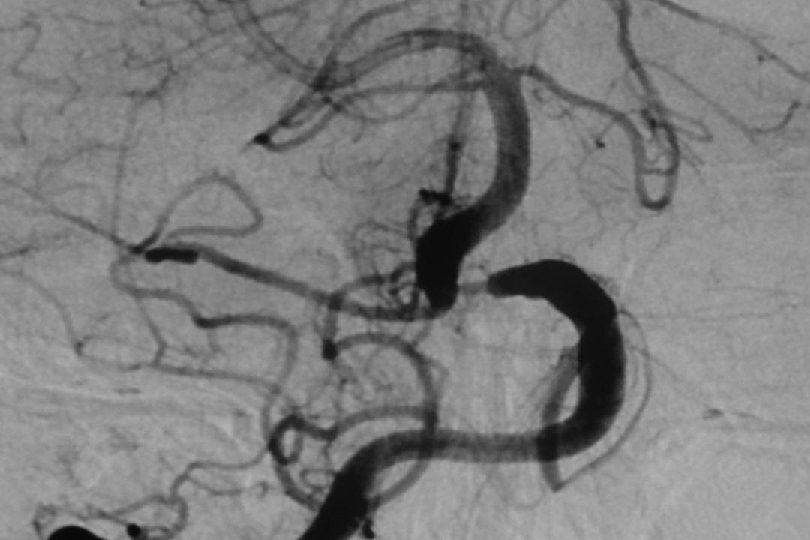

52 y kadın efektiv/test edilmiş ikili antiagregan ted altında iken multipl TIA Basit PTA sonrası

1. Yıl kontrol

1 yıl kontrol PTA Sonrası

PTA sonrası

. . 6 mm Solitaire ile Stentleme sonrası

66 mm Solitaire ile post stent

Post stent